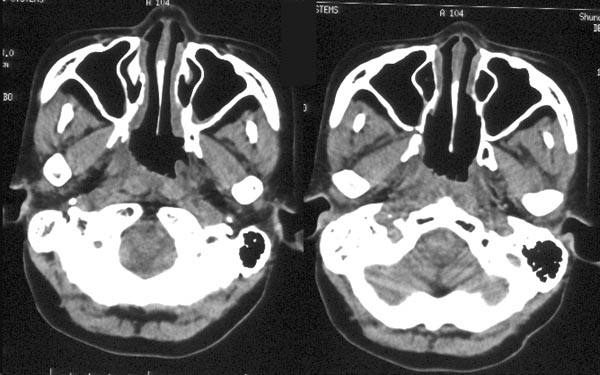

CCTV名家访谈专家张全安教授表示:鼻咽癌检查手段包括间接鼻咽镜检查,鼻咽纤维镜检查、鼻咽部CT检查和MRI检查。病理检查是确诊鼻咽癌的最重要依据。CT可以把鼻咽癌给查出来,但是在拍片的过程中病灶如果被遮挡的话,CT就不可以把鼻咽癌诊断出来,所以说CT只是有可能会发现疑似病灶。

根据患者的症状表现,做出初步判断,再利用前沿的鼻内窥镜以及X线或CT照片等,进行深入检查,较终确诊。>>>>>>在线免费咨询请点击>>>>>>